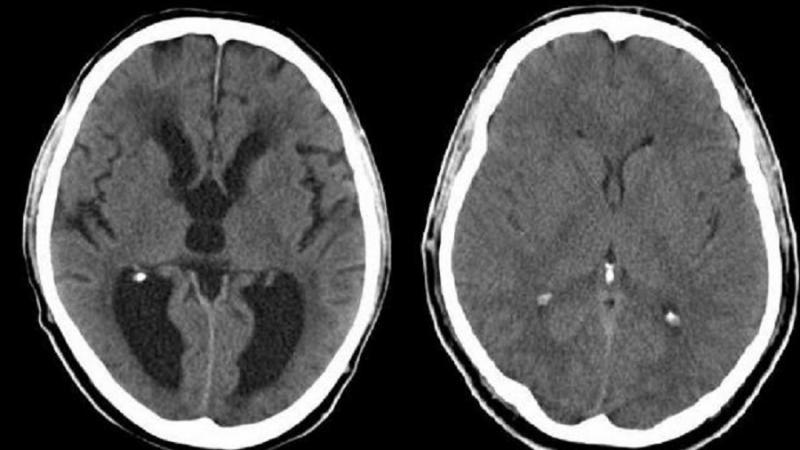

Esto es lo que debes saber sobre la hidrocefalia

La hidrocefalia es la acumulación de una cantidad excesiva de líquido cefalorraquídeo en el cerebro. Normalmente, este fluido protege y amortigua el cerebro. Sin embargo, demasiado líquido ejerce una presión dañina para el cerebro.